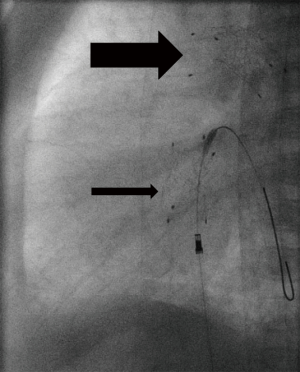

Critical aortic valve stenosis as well as aortic coarctation are defined by its associated LCO and failing heart function. The pressure gradient is usually not related to the severity of the lesion. Obstructions of the DA aggravate heart failure. Palliation strategies consist of re-opening the duct and/or of balloon valvular- or angioplasty. Balloon valvuloplasty needs guidewire crossing of the highly stenosed valve; several techniques and tips are described. A retrograde approach is the most common method (Figure 3A,B). In general, aortic valvuloplasty should be performed under rapid pacing to ensure balloon stability during inflation. The rapid pacing technique is usually not recommended in neonates with a critical aortic stenosis and low output heart failure, but this valve saving technique should be considered after a first valvuloplasty, if repetitive catheterization with balloon inflations have to be performed. Furthermore, stiff guide-wires, low pressure balloon catheters with a width of maximal 90% of the aortic anulus, but a triple length of the anulus size should be additionally considered, favoring satisfying results. Hemodynamic, angiographic and echocardiographic evaluations should be performed to assess the immediate result of the procedure. If necessary, the procedure has to be repeated with bigger balloons (26-29).